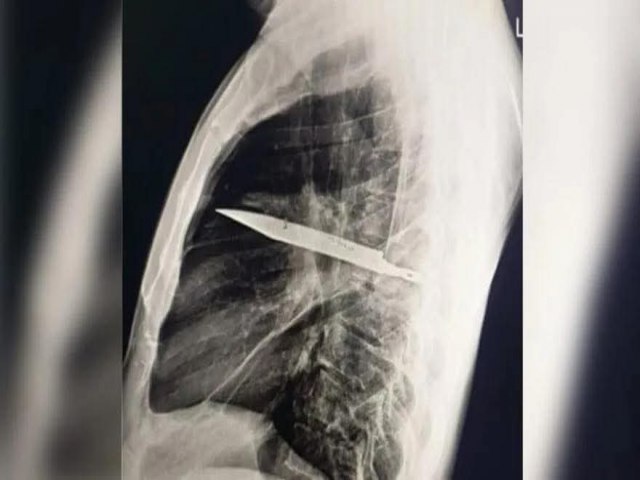

HOMEM VIVE QUASE 10 ANOS COM FACA NO PEITO E SÓ DESCOBRE APÓS EXAME

Um homem descobriu que viveu por oito anos com uma faca alojada no peito sem saber. A revelação veio depois que ele procurou atendimento médico na Tanzânia por causa de secreção com mau cheiro logo abaixo do mamilo direito.

No caso, publicado no Journal of Surgical Case Reports, o paciente (44 anos) relatou que não sentia dor no peito, dificuldade para respirar, tosse ou febre, e apresentava sinais vitais normais, o que deixou os médicos intrigados.

Enquanto os profissionais investigavam o caso, o paciente lembrou que, quase 10 anos antes, havia se machucado durante uma briga, sofrendo cortes no rosto, nas costas, no tórax e no abdômen. Na época, recebeu suturas, mas não passou por exames de imagem, já que não havia suspeita de que algum objeto tivesse permanecido no corpo.

O exame atual mostrou que uma lâmina estava presa ao lado direito do tórax, encostada à escápula. Apesar do tamanho, não atingiu órgãos vitais. Segundo os médicos, o acúmulo de pus foi causado pela presença do corpo estranho e por tecido danificado ao redor.

O homem passou por cirurgia para retirar a faca e drenar o pus. Ele ficou um dia na UTI e outros 10 internado em observação. A recuperação foi positiva, sem registro de novas complicações.